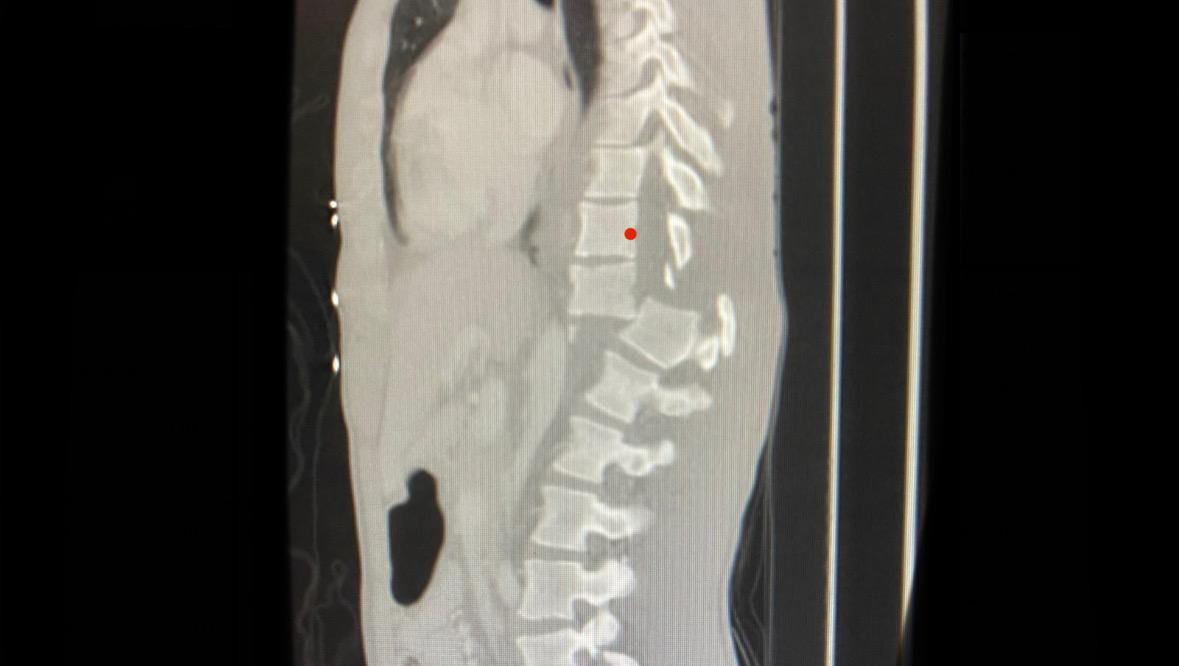

Una gran ola lo arrastró contra las rocas y lo hizo golpear fuertemente. Se fracturó la columna y ahora no siente la parte inferior de su cuerpo.

Facundo se encuentra internado y utiliza silla de ruedas para poder movilizarse.